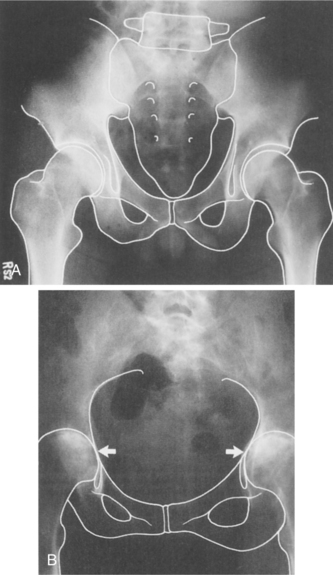

Conventional radiography, ultrasonography, and MRI studies are allowing more accurate diagnosis of RA. The earliest joint changes (periarticular swelling and cortical thinning with erosion at the margins of the articular cartilage and joint space narrowing) are seen on plain radiographs (Fig. 27-15). Screening cervical spine radiographs should be considered for all individuals with RA but especially for those with advanced peripheral joint disease.248

Figure 27-15 A, Radiograph of normal hips and pelvis. B, Radiograph of rheumatoid arthritis of the hips. Note the narrowed joint space (loss of articular cartilage) and periarticular bone density changes. (From McKinnis LN: Fundamentals of radiology for physical therapists. In Richardson JK, Iglarsh ZA, eds: Clinical orthopaedic physical therapy, Philadelphia, 1994, Saunders, p 673.)